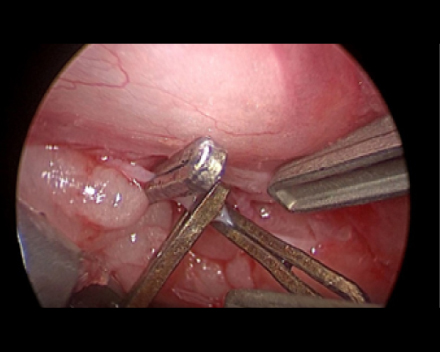

心膜切除も行っていきます。

心膜の一部を吊り上げて心膜と心臓の間にスペースを作ります

心膜の一部を切開して超音波メスで剥離していきます。

心臓の周りの剥離を進めていきます。

心膜を剥離し終わり、心臓が見えました。

これでしっかり拡張できるようになりました。